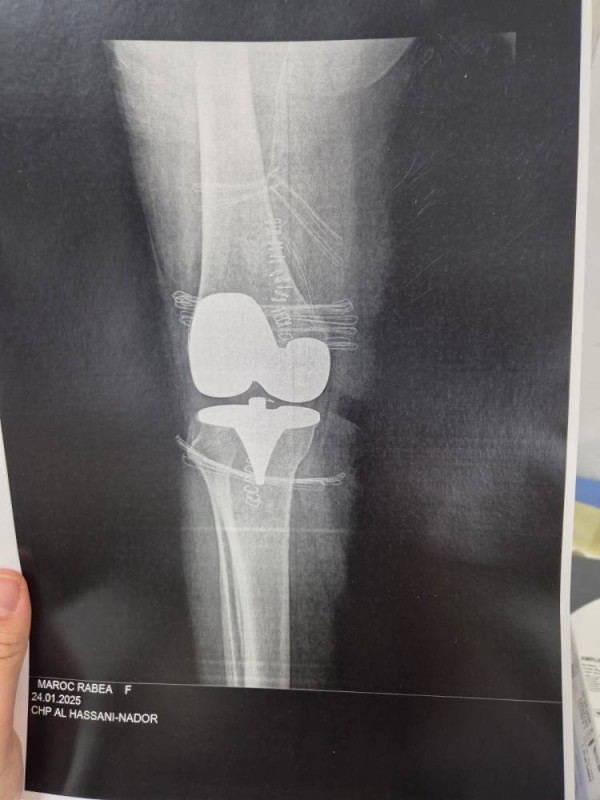

في إنجاز طبي متميز وغير مسبوق على مستوى المنطقة، تمكن فريق طبي وتمريضي متخصص في طب وجراحة العظام والمفاصل والإنعاش والتخدير بالمستشفى الحسني بمدينة الناظور، مؤخراً، من إعادة الساق اليسرى المبتورة لشاب تعرض لحادثة سير خطيرة، وذلك بعد عملية جراحية معقدة استغرقت حوالي أربع ساعات.

وأضاف الدكتور أمغار أن الفريق الطبي تم استدعاؤه على وجه السرعة في الساعة الرابعة صباحاً من يوم السبت، نظراً للحالة الاستعجالية للمصاب. وبجهود منسقة بين فريق جراحة العظام والمفاصل وفريق الإنعاش والتخدير، وبمساعدة طاقم تمريضي متخصص، تم إعادة الساق المبتورة بجميع مكوناتها إلى مكانها الطبيعي، كما تم علاج كسر بالساق اليمنى وجرح غائر على مستوى عروق الركبة اليمنى.